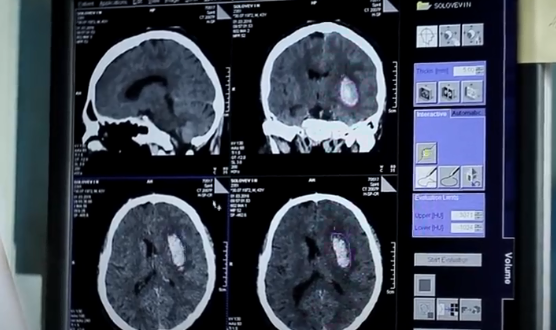

وتقوم عملية التشريح الرقمي أو المسح الإشعاعي لجثامين الوفيات باستخدام تقنيات الأشعة الإكلينيكية تحت إشراف فنيين مؤهلين ومدربين يطبقون الإجراءات والبروتوكولات المعمول بها وفق اللوائح الصادرة عن دائرة الصحة - أبوظبي بما يتماشى مع أفضل الممارسات العالمية التي تحترم حرمة الجثامين وتحافظ على الخصوصية، حيث يتم الإجراء دون المساس بالجثة أو تعريضها لتشريح فعلي ومن دون الحاجة لفتح أو إخراج الجثة من كيس الإخلاء الذي يتم استلامها فيه.

وكانت الإمارة قد استعانت بتقنية التشريح الرقمي المتوفرة في المشرحة المركزية بمدينة أبوظبي في التقصي عن حالات الوفاة التي تظهر عليها مؤشرات تغير في الرئة، ما قد يدُل على احتمالية الإصابة بفيروس كوفيد-19، وذلك بهدف حماية المتعاملين مع الجثمان ولتقصي وفحص المخالطين للمتوفى لضمان سلامتهم وصحتهم وصحة من حولهم.

ويسهم التشريح الرقمي في تحقيق جملة من الأهداف الهامة بما في ذلك تحديد الإصابات والكسور بشكل دقيق، الكشف عن أي نزف دموي في الجمجمة أو تجاويف الجسم ما يسهم في تحديد سبب الوفاة، التعرف على هوية وجنس المتوفى والفئة العمرية التي ينتمي إليها وخصوصاً في حالات الأزمات والكوارث، الكشف عن آثار العنف ضد الأطفال والقصّر المتوفين، الكشف عن التغيرات الناتجة عن تأثر الجسم من الاختلاف المفاجئ للضغط لا سيما في حوادث الغوص العميق، والاستعاضة عن الفحص التشريحي في بعض الحالات.

وبدأ استخدام تقنية التشريح الرقمي منذ أكثر من عام، حيث تم توظيفها في التعامل مع أكثر من 700 حالة حتى تاريخه، ويبلغ الوقت المستغرق للتشريح الافتراضي من 15 إلى 30 دقيقة كحد أقصى.